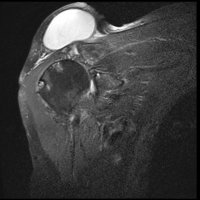

On physical examination, an AC joint cyst is a palpable fluid-filled mass. MRI scanning or a shoulder arthrogram should be obtained to evaluate the shoulder. Unenhanced MRI scans showing a large rotator cuff tear, a degenerated AC joint, and a large subcutaneous cyst adjacent to the AC joint is virtually patognomonic for the disease. Contrast administration on MR arthrogram will show the synovial fluid or intra-articular contrast extravasates from the glenohumeral joint into the subacromial bursa, into the AC joint, and then into an overlying cystic mass when a full-thickness rotator cuff tear is present, resembling a geyser spouting upwards.